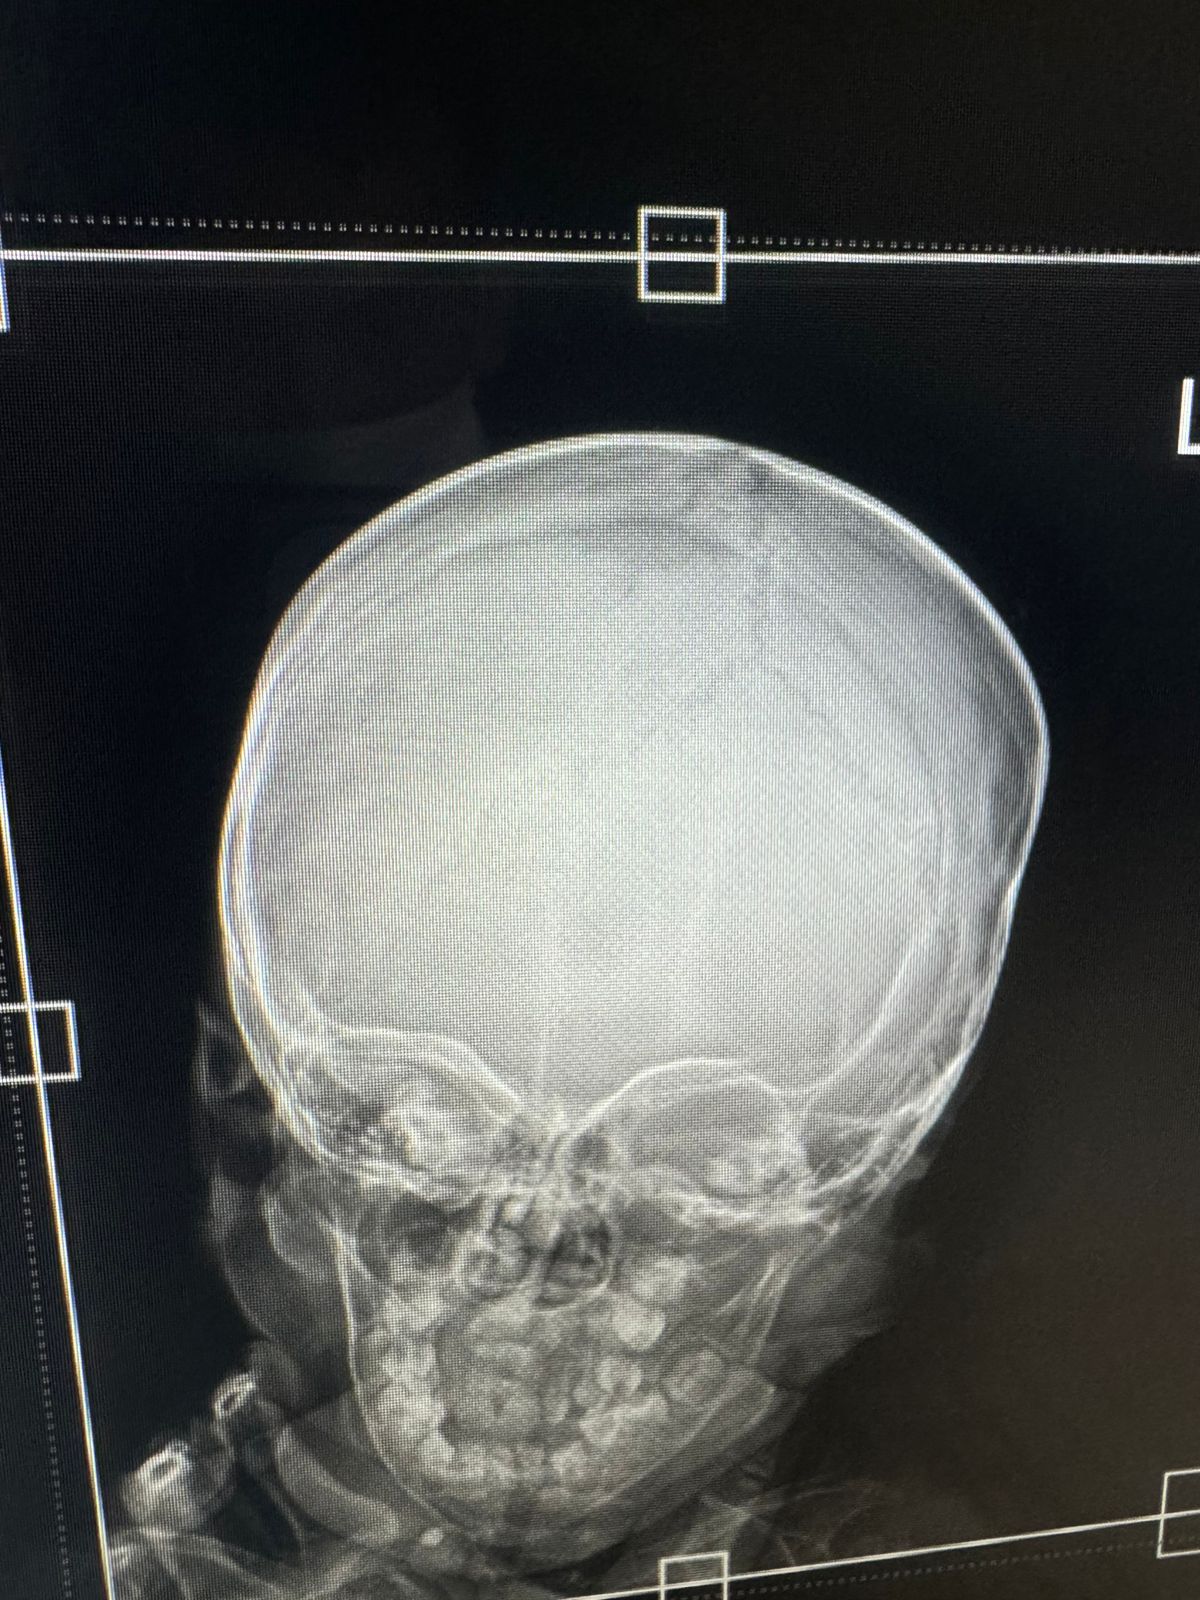

Дочке 1.6. Верхние зубы все почти прорезались. Проблема с нижними. Когда нижние резцы прорезались они вылезли не посередине. А а чуть правее. На фото можно увидеть. Потом вылез с права без пары боковой резец. А пары так и нету. И три зуба по середине кривые. Я думала что его нету. И другие зубы вылезли как папало так как мест много. Вылезли уже клыки. На него мест даже не осталось. Недавно дочка ударила голову. И мы делали снимок головы. И там как будто я увидела этот боковой резец.( отметила на фото) Или это просто тень. Не могу понять. Уже устала ждать и нервничать. А рентген зубов сделать она не даст. Очень уж капризная